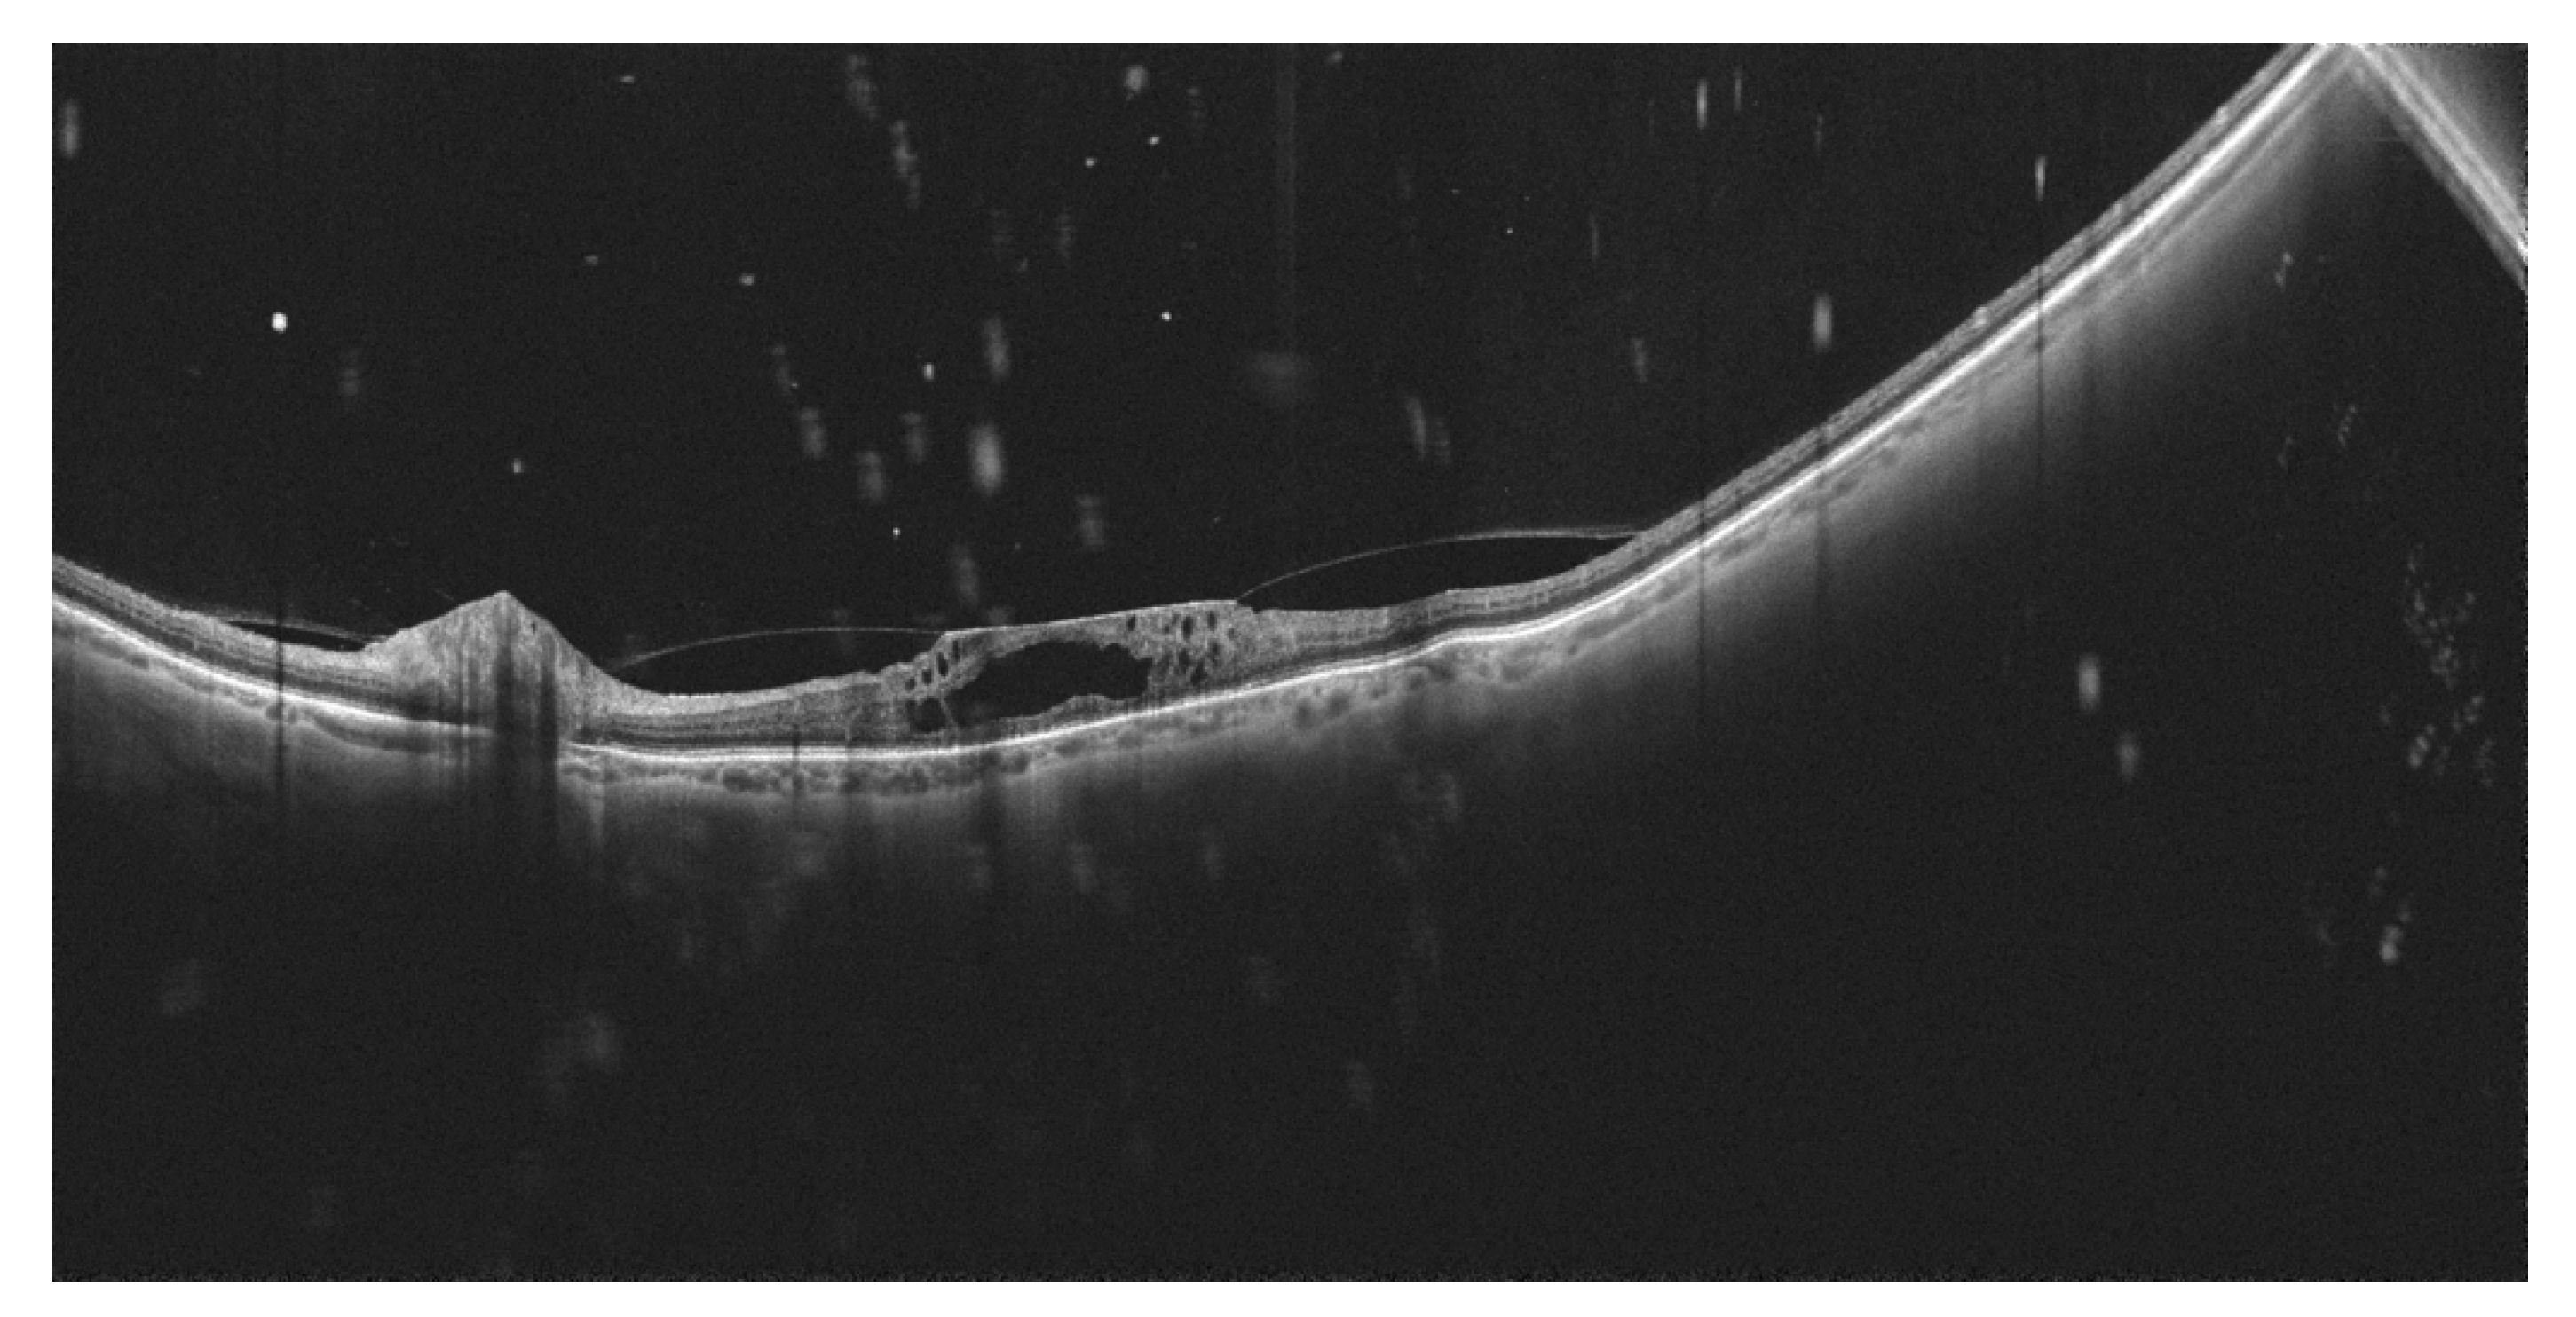

- Wright, P.H.; Khalid, H.; Keane, P.A. The utility of wide-field optical coherence tomography angiography in diagnosis and monitoring of proliferative diabetic retinopathy in pregnancy. Am. J. Ophthalmol. Case Rep. 2022, 25, 101280. [Google Scholar] [CrossRef]